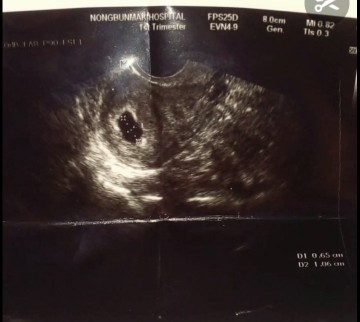

6วิค เจอแค่ถุงการตั้งครรภ์ ไม่เจอตัวเด็ก

ประจำเดือนขาด2เดือน อัลตร้าซาว อายุครรภ์ของถุง 6วิค ไม่เจอตัวน้อง หมอบอกเสี่ยงท้องลม มีใครเป็นแบบนี้ไหมคะ